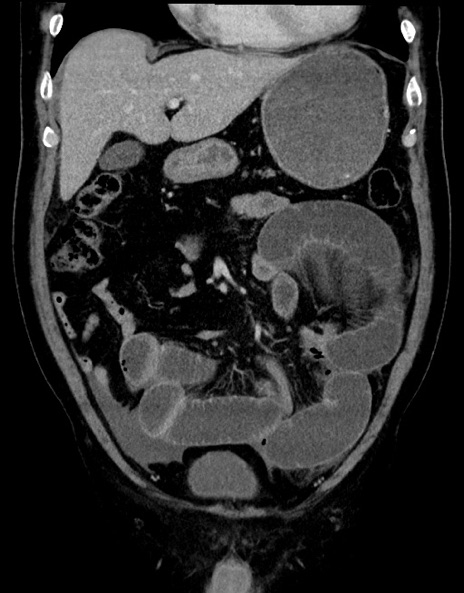

症例15(冠状断像)

【症例】70歳代男性

【主訴】腹痛

【現病歴】今朝から腹痛あり。全体的に痛い。特に左上の方。排ガスが今日はない。冷や汗が出る。

【既往歴】直腸癌術後

【身体所見】左側腹部〜上腹部に圧痛あり。腹膜刺激症状明らかなではない。軽度反跳痛。左下腹部に術後瘢痕あり。

【データ】WBC 7700、CRP 0.02